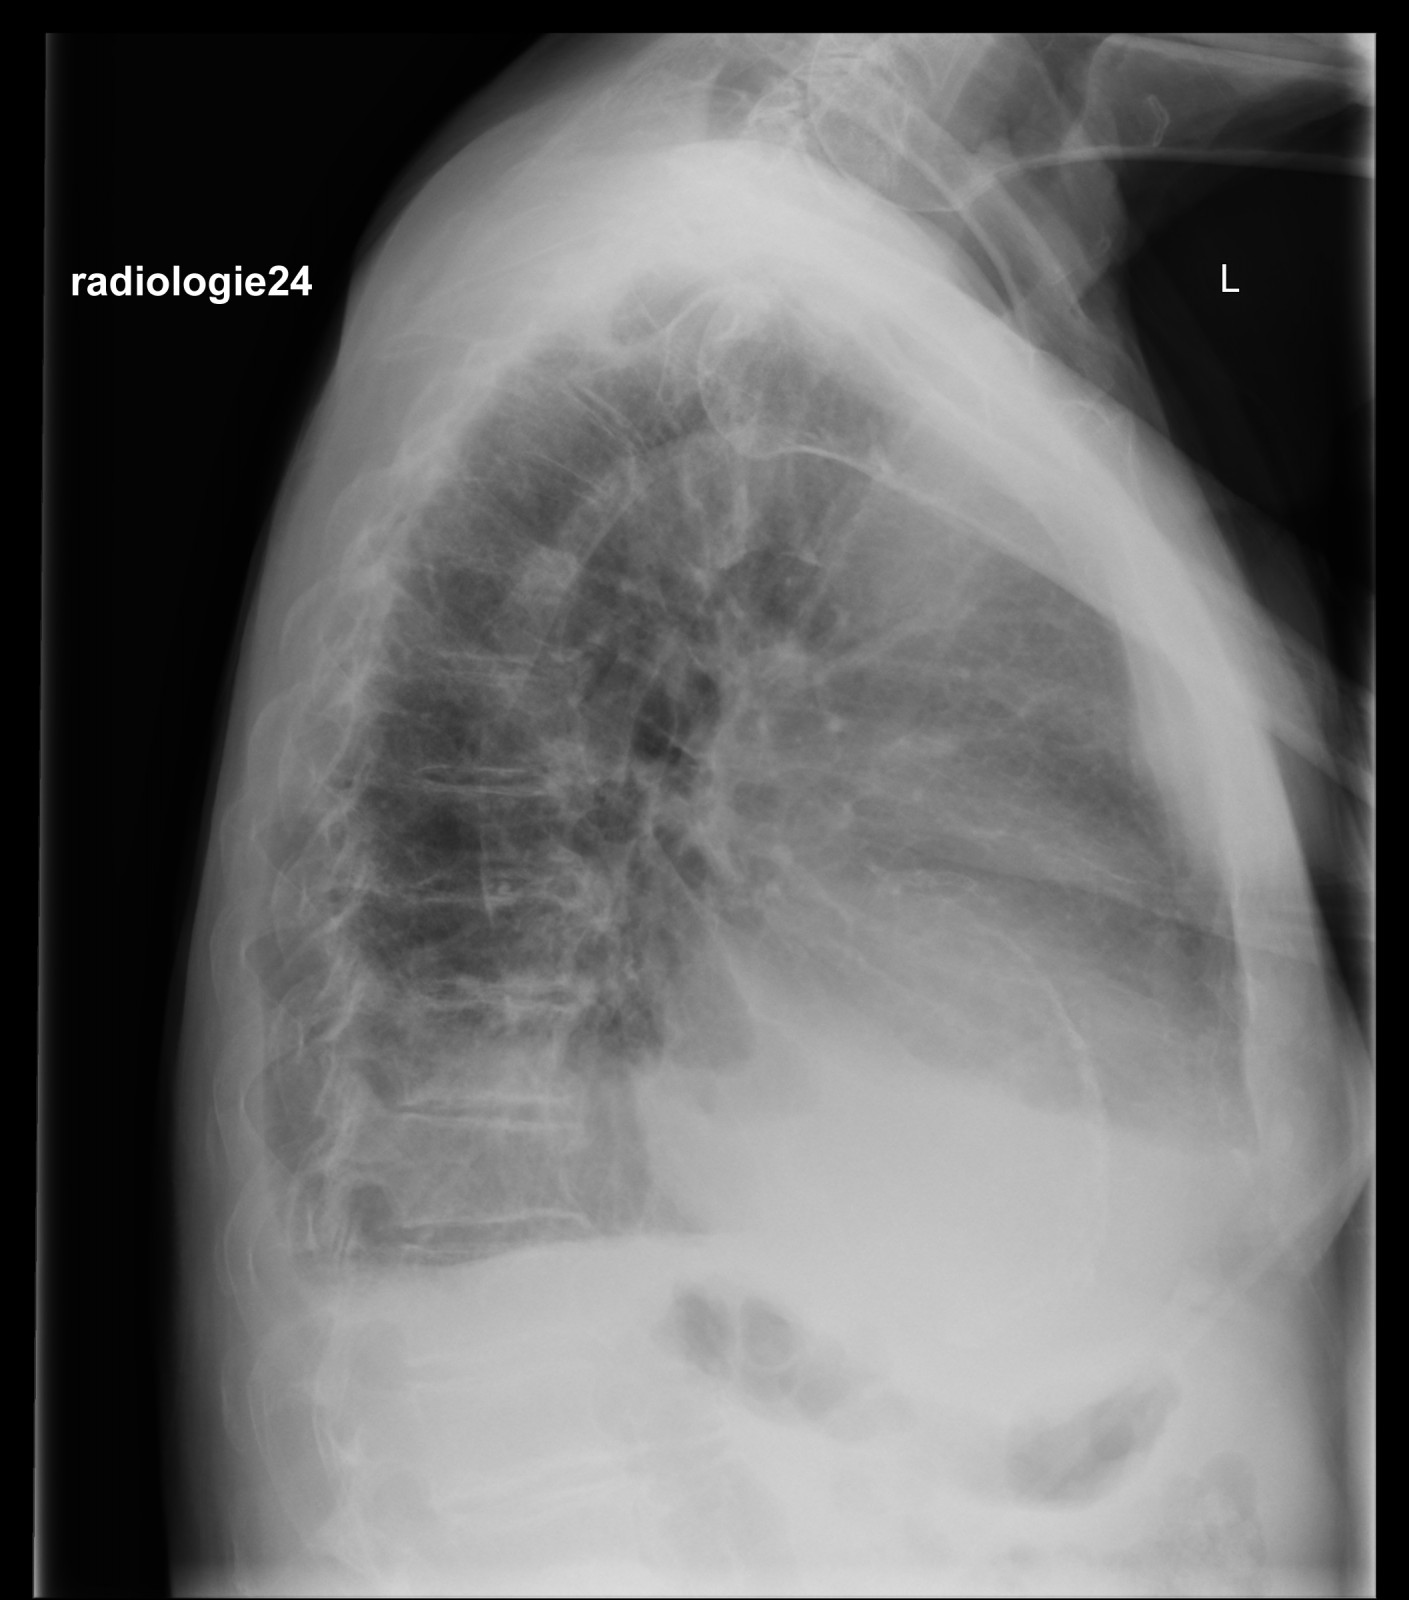

Röntgenfall des Monats Februar 2018 mit Auflösung

75 jähriger Patient Zunehmende Belastungsdyspnoe. Ihre Diagnose? Nebenbefunde?

Bild vergrössern

Link zur Auflösung mit ausführlichem Befund:

https://www.radiologie24.ch/radiologie-mediathek/roentgenfall_des_monats